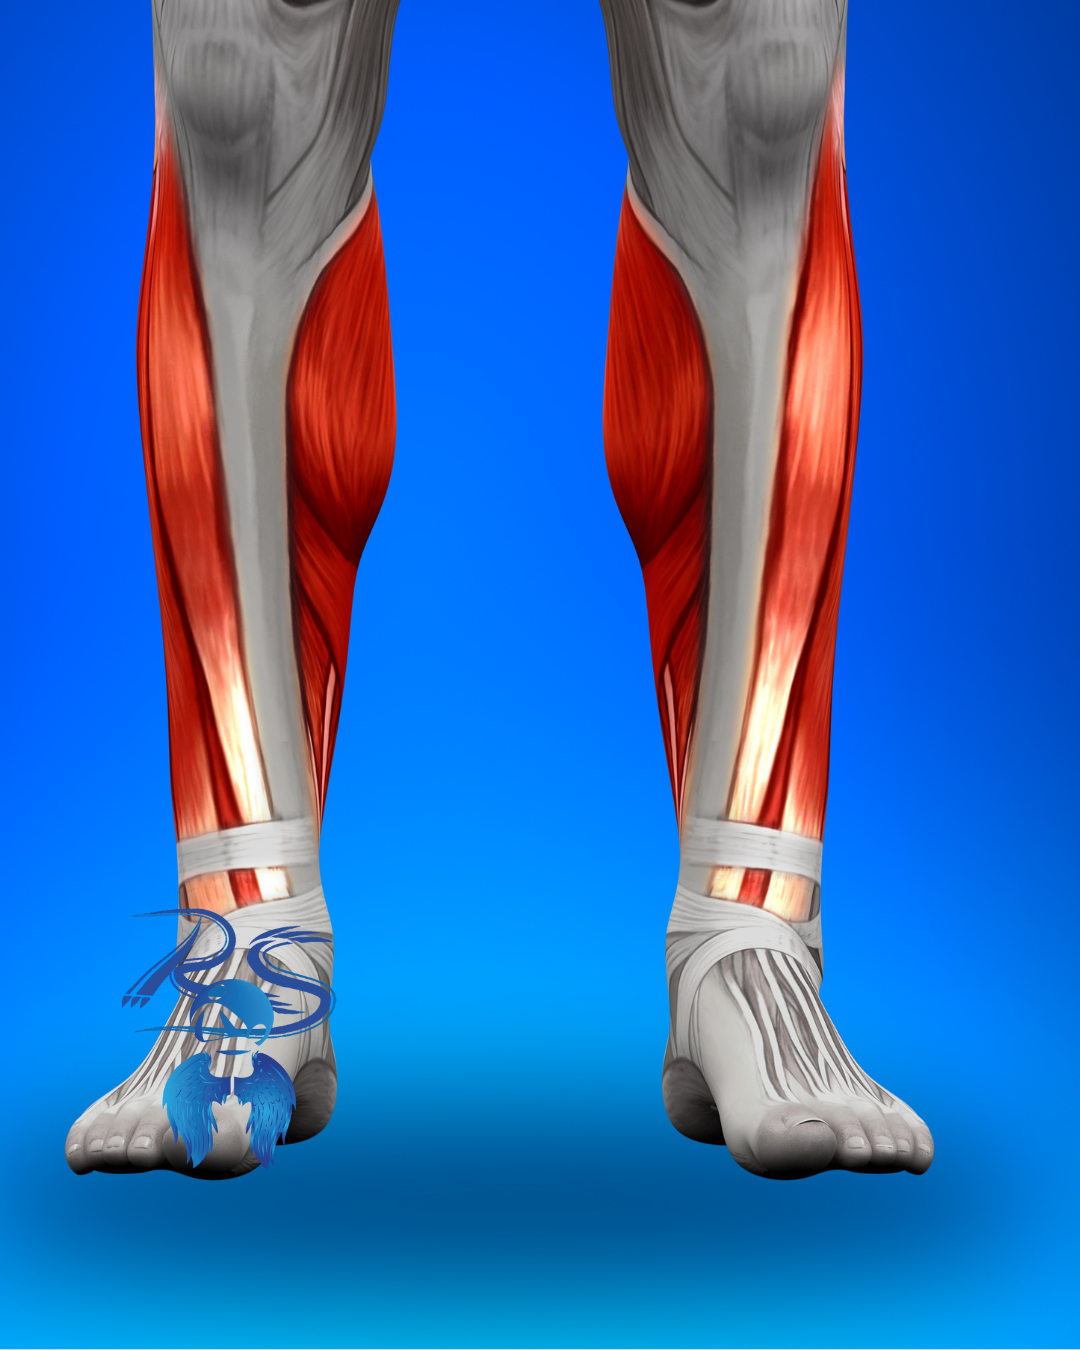

Tibial anterior: presión por agujetas ajustadas

El tibial anterior se ve afectado cuando el empeine recibe presión constante.

Molestia en tobillo y espinilla

Cómo ayuda el masaje terapéutico: La liberación de puntos gatillo disminuye la sobrecarga muscular y mejora la mecánica de la pisada.

Peroneos: compensación y desequilibrio

Cuando el pie no se mueve libremente, los músculos laterales de la pierna compensan el esfuerzo.

- Cansancio en la pierna

Cómo ayuda el masaje terapéutico: El trabajo profundo equilibra la musculatura y previene lesiones.